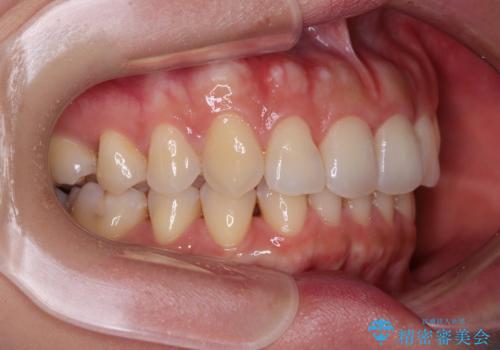

- 捻れた前歯が飛び出しており、口が閉じにくいとのことで来院された患者様です。

出っ歯というわけではないものの、前歯の捻転により口唇が押し出されている状態でした。

親知らずを抜去し、歯列全体を後方に移動させつつ、IPR(歯と歯の間を削る)でスペースを獲得し、インビザラインを用いて叢生を解消しながら前歯の突出を改善することとしました。

骨格的に上下正中がずれていたため、奥歯がしっかりと噛み合うか心配でしたが、ずれているなりに、しっかりとした咬み合わせとなりました。